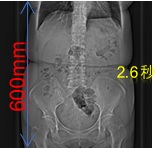

• 高速撮影

シーメンス社のテクノロジーにより、全身領域において高速スパイラルスキャンが可能です。

高速で230mm/秒で撮影することができ、例としておなか60cmの範囲を撮影するとした場合、約3秒の息止めで撮影することが可能です(検査の種類、目的により異なります)

高速撮影